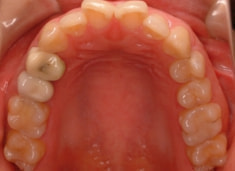

治療前